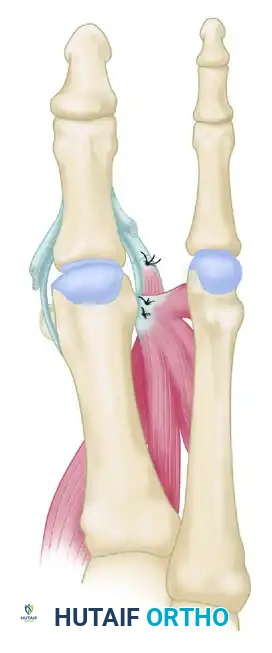

Surgical Steps of the Hawkins Transfer

- Lateral Release: The lateral structures (lateral capsule, lateral collateral ligament) are meticulously released to mobilize the joint.

- Tendon Harvesting and Routing: The muscle-tendon unit of the abductor hallucis is identified medially, detached from its insertion, and mobilized. It is then transferred to the base of the proximal phalanx.

- Plantar Routing: Crucially, the tendon must be routed plantar to the transverse intermetatarsal ligament. It is passed through a created long bone tunnel in the proximal phalanx.

FIGURE 81-81B: Repositioning of the abductor hallucis. The tendon is routed to replace the function of the deficient adductor hallucis.